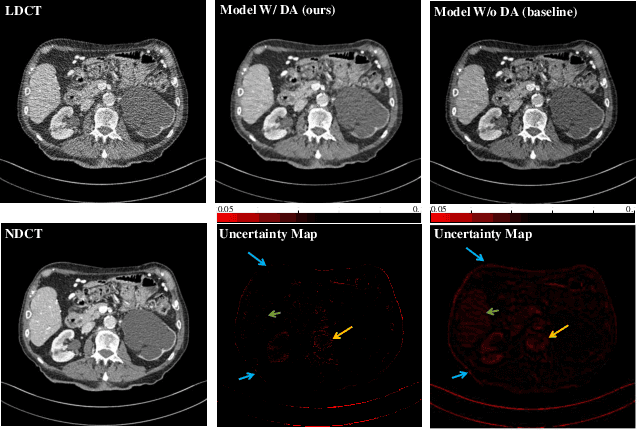

Abstract:In this work, we tackle the problem of robust computed tomography (CT) reconstruction issue under a cross-domain scenario, i.e., the training CT data as the source domain and the testing CT data as the target domain are collected from different anatomical regions. Due to the mismatches of the scan region and corresponding scan protocols, there is usually a difference of noise distributions between source and target domains (a.k.a. noise distribution shifts), resulting in a catastrophic deterioration of the reconstruction performance on target domain. To render a robust cross-domain CT reconstruction performance, instead of using deterministic models (e.g., convolutional neural network), a Bayesian-endowed probabilistic framework is introduced into robust cross-domain CT reconstruction task due to its impressive robustness. Under this probabilistic framework, we propose to alleviate the noise distribution shifts between source and target domains via implicit noise modeling schemes in the latent space and image space, respectively. Specifically, a novel Bayesian noise uncertainty alignment (BNUA) method is proposed to conduct implicit noise distribution modeling and alignment in the latent space. Moreover, an adversarial learning manner is imposed to reduce the discrepancy of noise distribution between two domains in the image space via a novel residual distribution alignment (RDA). Extensive experiments on the head and abdomen scans show that our proposed method can achieve a better performance of robust cross-domain CT reconstruction than existing approaches in terms of both quantitative and qualitative results.